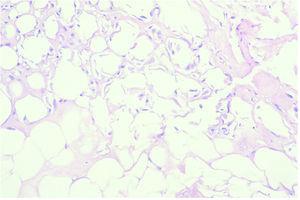

Los casos biopsiados más tardíamente, con mayor evolución mostraron fibrosis septal, necrosis de adipocitos e imágenes de degeneración lipomembranosa de la grasa (fig. 5), sin existir cambios importantes en dermis y epidermis salvo la presencia ocasional de siringometaplasia escamosa ecrina (figs. 6A y B).

Fig. 5.--Imágenes de degeneración lipomembran osa de la grasa. (Hematoxilina-eosina, ×20.)

Fig. 6.--Fibrosis septal (A) y necrosis de adipocitos (B). (Hematoxilina-eosina, ×10.)

En las fases avanzadas (primer mes tras la extravasación) se encuentra fibrosis septal, ulceración epidérmica y necrosis de adipocitos con degeneración lipomembranosa de la grasa. En las fases tardías (varios meses después de la extravasación) pueden llegarse a formar pseudoquistes de necrosis grasa con fibrosis perilesional.